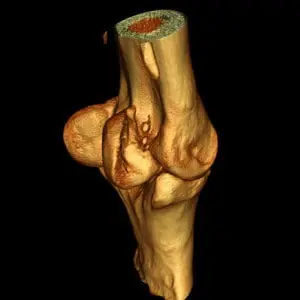

Die Computertomographie ist, ähnlich wie die Magnetresonanztomographie, ein Schnittbildverfahren. Anders als bei der MRT entstehen die CT-Bilder mit Hilfe von Röntgenstrahlen. Dabei wird das Pferd schichtweise durchleuchtet, und aus den zahlreichen Einzelaufnahmen errechnet ein Computer ein dreidimensionales Bild der untersuchten Region. So lassen sich selbst sehr kleine Veränderungen an Knochen oder Weichteilen sichtbar machen, die mit klassischen Röntgenbildern nicht erkennbar wären. Bei Bedarf kann zusätzlich ein Kontrastmittel eingesetzt werden, um bestimmte Strukturen noch besser darzustellen.

Computertomographische Untersuchungen der oberen Gliedmaße und hinteren Abschnitten der Halswirbelsäule benötigen eine Vollnarkose, bei der die Pferde wie bei einer Operation in Vollnarkose gelegt werden und anschließend durch den OP-Raum, in den direkt angrenzenden CT-Raum gefahren werden können. Dies ermöglicht einen reibungslosen Verlauf der Vollnarkose und ermöglicht ebenfalls Operationen unter CT Kontrolle durchzuführen.